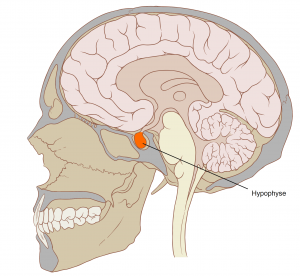

Die Hypophyse oder Hirnanhangsdrüse ist ungefähr nur so groß wie ein Kirschkern, ist aber zuständig für die Hauptsteuerung des gesamten menschlichen Hormonhaushaltes. Die Hypophyse bildet Botenstoffe, die den Hormonhaushalt im Körper regulieren. Störungen dieser Regulation können massive Auswirkungen auf die Betroffenen haben. Bei Tumoren der Hirnanhangsdrüse muss daher zwischen hormonproduzierenden und hormoninaktiven Tumoren unterschieden werden.

Bildquelle: Patrick J. Lynch, original Image: Skull and Brain sagittal.svg